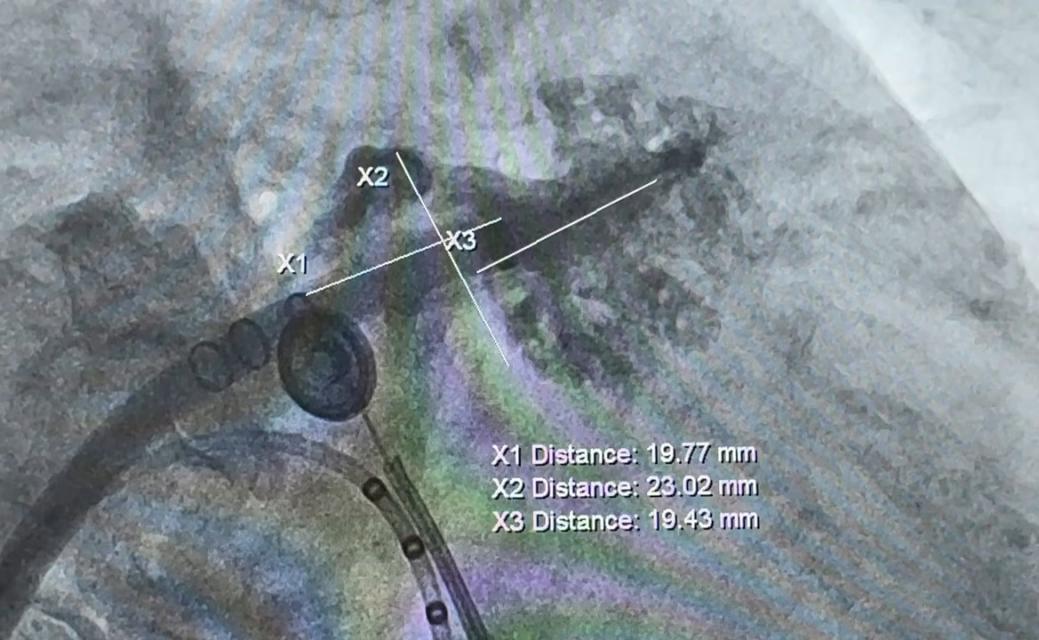

之后在ICE和DSA引导下,充分评估测量左心耳形态和大小,完成左心耳封堵手术。术后患者恢复良好。

左心耳测量